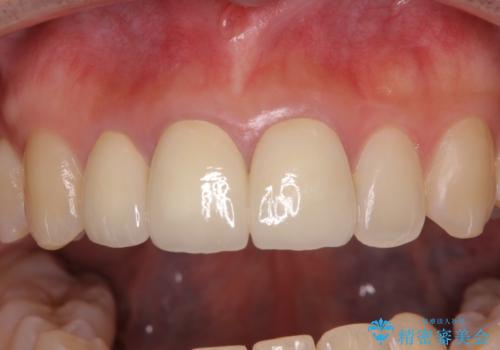

前歯の黒い縁を綺麗にしたい 前歯のオールセラミック

金属を除去したことで、周りと調和した自然な色合いとなり、クラウンの際の位置も歯肉に少し入り込む位置となっているためまるで本物の歯のような仕上がりとなりました。